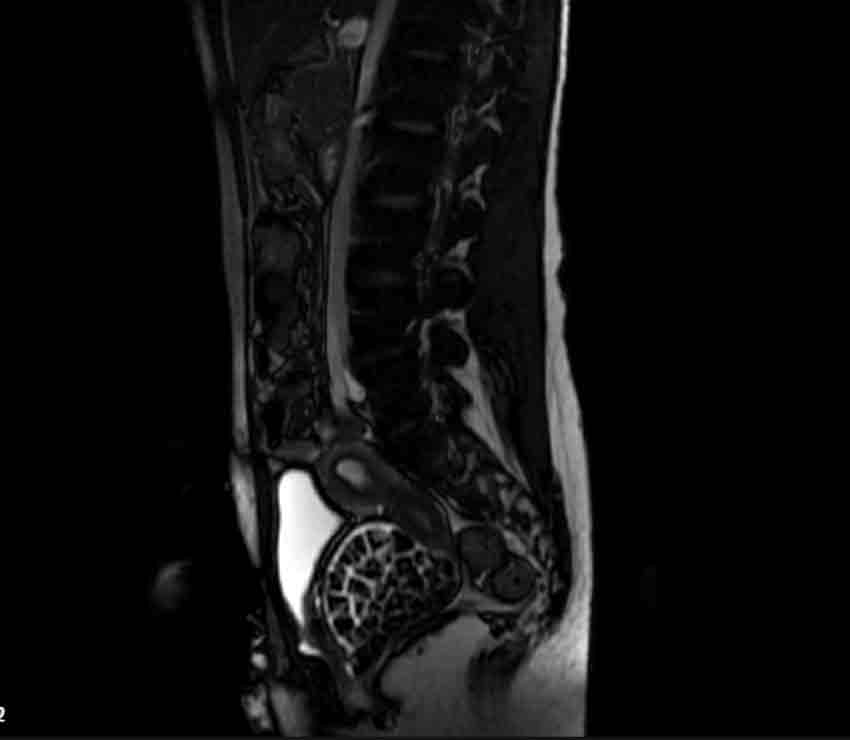

Hastasının durumuna yönelik konuşan Üroloji Uzmanı Doç. Dr. Erkan Erkan, "Hastamızın 2004 yılında doğduğunu ardından doğar doğmaz ekstrofi vezika dediğimiz 50 binde bir görülen bir anomaliden dolayı art arda ameliyatlar geçirdiğini öğrendik. 10 yaşında yine bir ameliyat geçirmişti, gerekli görüntüleme ve tetkiklerimizi yaptırdık. Normalde mesanesinin olması gereken yerin hemen arka kısmında taşlarla dolu bir kese olduğunu gördük, bunun üzerine ek görüntülemeler; MR çektirdik. Hastamız çelişkili açıklamalar almıştı, kendi radyolojik kliniğimiz ve edindiğimiz konsültasyonlarda taşların mesanede değil vajinal boşlukta oluştuğunu düşündük, bir planlama yaptık. Kadın doğum hocamızın da çabasıyla taşları tamamen temizledik ardından ileride normal bir hayat sürmesi bakımından oraya plastik cerrahi yaptık. 287 adet taş çıkardık, pratikte gerçekten görünce çok şaşırdık çünkü bu aynı zamanda literatürde çok nadir görülen bir olay. Biz ameliyata hazırlanırken de teorik olarak biraz araştırdık. Literatürde gördüğümüz kadarıyla buna benzer bu tanıma uyan bir vaka vardı. Literatürde sanırım yayınlanmış 2’nci vaka olacak. Farkındalık çok önemli, bilinçli bir hastamız vardı. Doğumsal anomaliyle doğan çocuklarımızda ileride bunlara bağlı bazı sıkıntılar çıkabileceğinin öngörülmesi lazım. İlgili tedavilerini alsalar bile düzenli takiplere gelmeleri gerekiyor. İleride eğer dikkat etmezse ki zannetmiyorum, tekrarlayabilir. Bu rahatsızlık ekstrofi vezikal epispadias durumu çok nadir bir durum" dedi.

Genç kızın uzun süredir devam eden karın ağrısı olduğunu söyleyerek sözlerine başlayan Jinekolojik Onkoloji Uzmanı Op. Dr. Emin Erhan Dönmez, "Mesane taşları olduğu düşünülerek daha büyük bir hastaneye refere edilmiş. Aramızda mini bir konsey yaparak muayene ettik. Vajen bir hazne görevi görerek orada durağan bir idrar, uzun süre beklediği için idrar içindeki minerallerde çökerek taşlar oluşmuş. Mesanedeki idrarın vajene akmış olabileceği ve vajende göllenen idrar nedeniyle taşların burada oluşacağını düşündük, ameliyatımızı planladık. Ameliyata tanı amaçlı girmiştik, sistoskopi (Mesane gibi idrar yollarını kapsayan kısımlardaki rahatsızlıkların teşhis ve tedavisinde kullanılan endoskopik bir yöntem) dediğimiz ameliyatı Erkan Hocam ile birlikte gerçekleştirdik. Önce mesaneyi bir görüntüledik, mesane tabanına yaklaşık 2-3 cm’lik bir alandan vajene fistülize olduğunu gördük. Mesaneden vajene geçtiğimiz esnada tüm vajenin taşlarla dolu olduğunu gördük. Tanı amacıyla girdiğimiz ameliyatta her şey de olağan gittiği için tedaviye geçtik. Taşların çıkabileceği kadar bir genişlik sağladık. Daha sonra yaklaşık en büyüğü 2,5 cm boyutlarında olan, irili ufaklı 287 tane taşı ameliyat esnasında çıkarmış olduk. Taşların tekrarlamaması için idrarın göllenmemesi, en azından dışarıya rahatça boşalabilmesi için vajinal rekonstrüksiyonu sağladık. Ameliyatta da herhangi bir problem yaşamadık. Literatürü Erkan Hocam ile birlikte değerlendirmiştik. Primer olarak vajende birikmiş olan bu kadar çok sayıda taşla ilgili bir makale görmedik, rastlamadık" dedi.